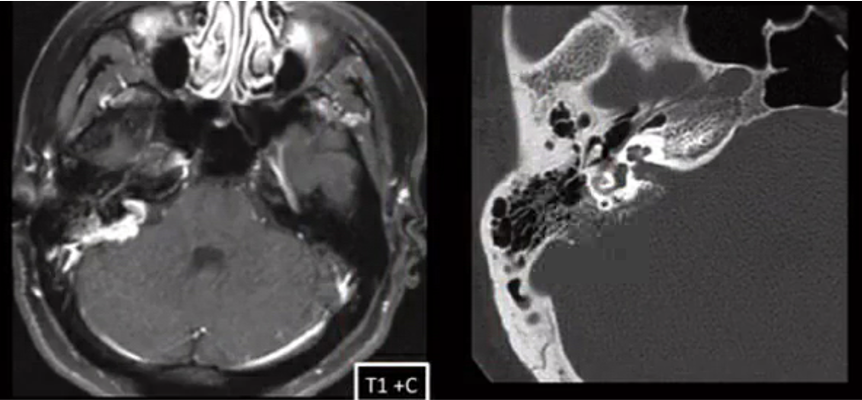

SCC of the EAC on CT and MR

axial bone algorithm CT shows soft tissue density in the EAC with osseous erosion. MR demostrates soft tissue enhancement.

Bone destruction and soft tissue invasion = aggressive malignancy